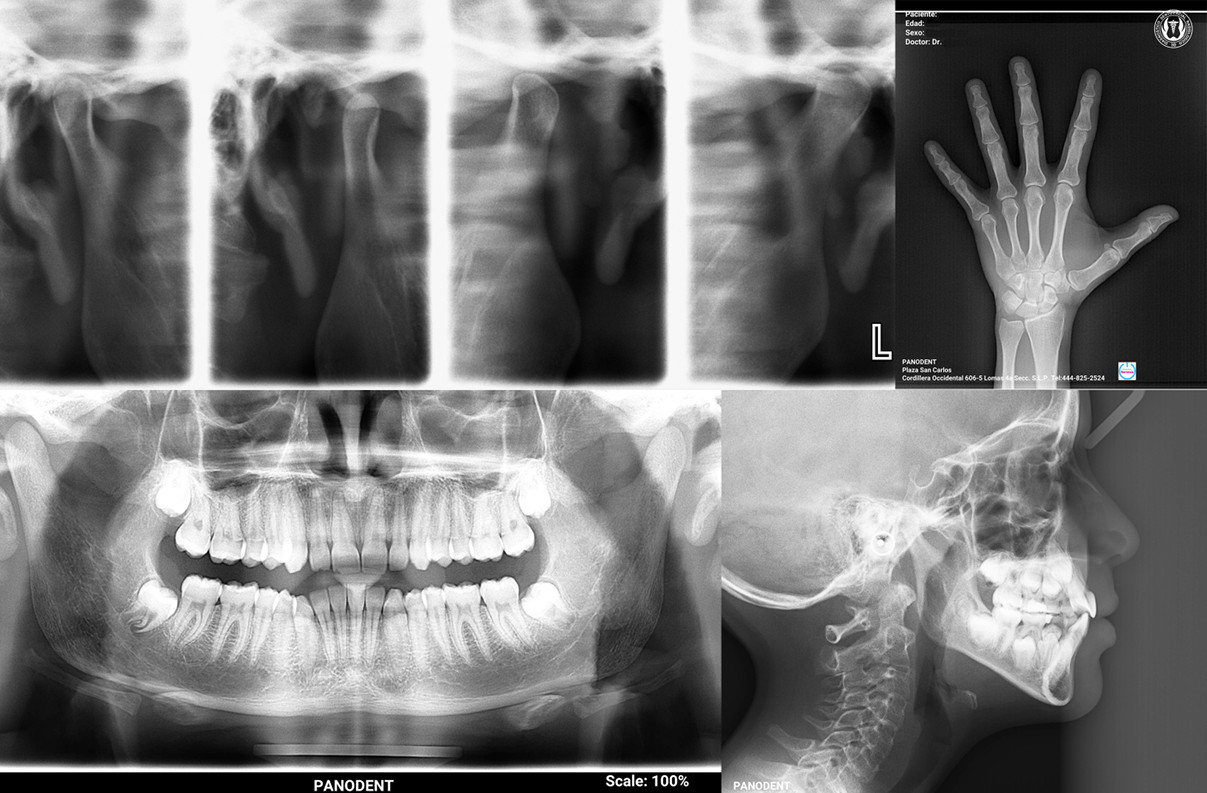

Panodent está equipado con la más avanzada tecnología para ofrecer los servicios en Radiología de alta definición, necesarios para la nueva Odontología Digital, permitiendo al profesionista planificar cada tratamiento en las mejores condiciones, y poder ofrecer la máxima Precisión y Calidad diagnóstica.

Los modelos de estudio constituyen un elemento de primer orden para el tratamiento ortodóncico, no solo por su valor diagnóstico, sino porque nos ofrece la posibilidad de comparar el caso que se está tratando.

Además, se hacen imprescindibles los modelos de trabajo en la confección, como su nombre lo indica, de los diferentes aparatos ortodóncicos.